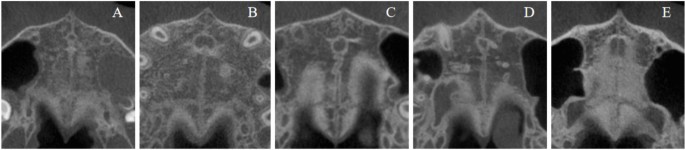

Images of MPS stages based on Angelieri’s five-stage system (A–E). Midpalatal suture maturation stages based on Angelieri’s classification system. Representative CBCT coronal sections showing the five stages of midpalatal suture development: Stage A shows straight high-density sutural line; Stage B displays scalloped appearance with occasional parallel lines; Stage C presents two parallel scalloped lines with small separations; Stage D demonstrates fusion in posterior region with visible suture anteriorly; Stage E shows complete fusion with no visible suture.

MPS Maturation Staging (MPS Stage): As shown in Figure 1, MPS maturation was classified using Angelieri’s five-stage system13: Stage A (straight high-density sutural line), Stage B (scalloped appearance with occasional parallel lines), Stage C (two parallel scalloped lines with small separations), Stage D (fusion in posterior region with visible suture anteriorly), and Stage E (complete fusion with no visible suture).